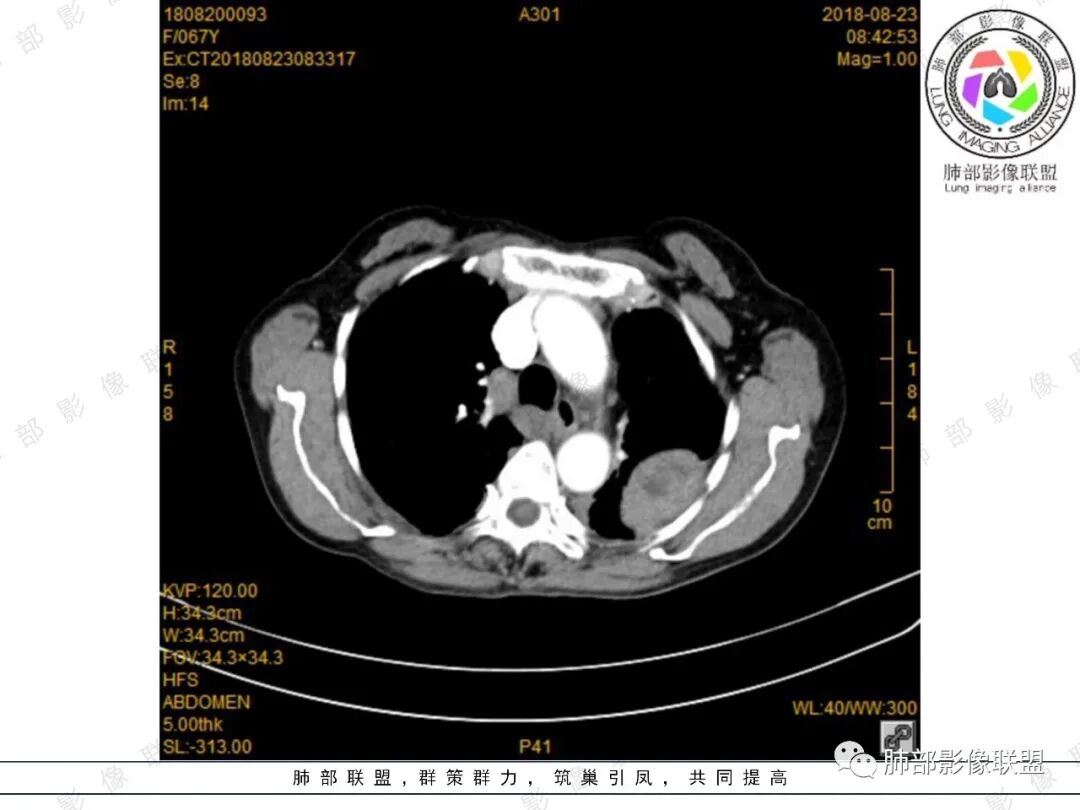

大雄:增强确实看的有些奇怪,胸部的无强化,脾内的轻度强化。如果是EMH,按理有强化的,除非全部脂肪变性了。虽然不是EMH好发位置,但也可以。淋巴瘤强化也不符合,胸部的这个形态也不太像淋巴瘤。如果只是单纯脾大,那么孤立的EMH也很少见。

大雄:定位肺外  无明显强化  有坏死或囊变   脾大

King:很有意思,能想到髓外造血的老师水平高。首先定位胸膜可能大,倾向良性,渐进强化,脾脏多发占位,渐进延迟强化,两者强化有类似之处,倾向一元论。病灶边缘斑点钙化,淋巴瘤少有。消化道肿瘤转移,胸膜孤立转移少有。恶性孤纤伴脾脏转移,也少。贫血,髓外造血,可以,但胸膜相对少见。副脾,少见部位,强化度差点。总之一元论的话像个少见病变,难以确定,就排个序吧。一元:髓外造血>副脾>淋巴瘤。二元:孤纤+血管瘤/错构瘤.

joyzhy:脾脏占位增大,特点延迟期强化和脾脏一致,考虑血管瘤。胸部占位,考虑肺外,鞘瘤或髓外造血。

4、密度、信号及骨骼情况:由于髓外造血组织呈缓慢的代偿性增生,因而病灶边缘光滑。又因血供较好,病变无囊变和钙化。EMH由不同阶段的造血细胞组成,平扫呈等或稍高密度,增强扫描处于造血活跃期的肿块呈中度~明显强化,处于缓解期的肿块,由于脂肪变性无明显强化。